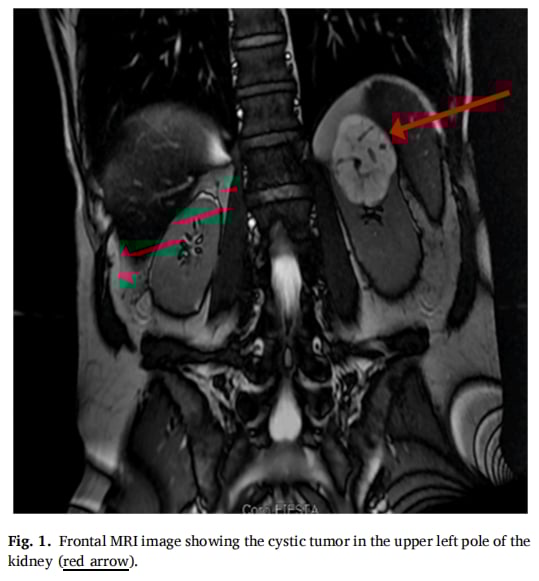

患者,39岁男性,既往身体状况良好。因铁蛋白浓度高达2000 μg/L(正常值低于300 μg/L)而入院。为了查明高铁蛋白血症的根本原因,医生安排了腹盆腔扫描,结果意外发现其左肾上极存在一个约6厘米的囊性肿块。经过进一步的MRI检查,该肿块被归类为Bosniak III类,这通常意味着其具有较高的恶性风险。

▲图1 正面MRI图像显示肾脏左上极存在囊性肿瘤